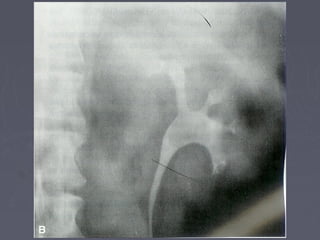

Mis imágenes2005-04 (abr)litiais.jpg